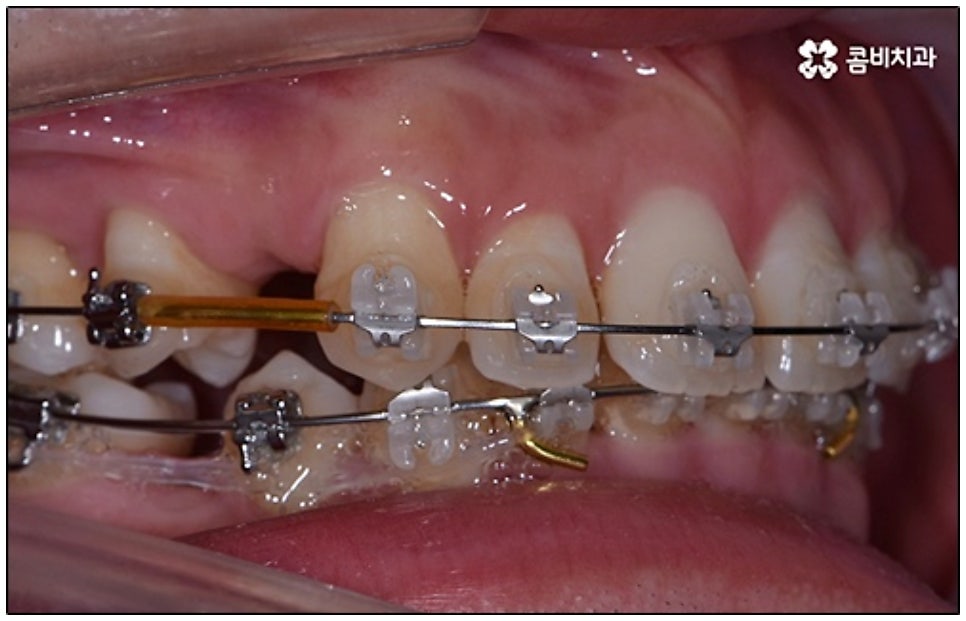

요즘 가장 많이 쓰이는 것은 클리피씨교정 장치로, 브라켓에 자체적으로 여닫을 수 있는 클립(뚜껑)이 있어 보다 손쉽게 와이어를 장착하거나 제거할 수 있어요. 이와 같은 자가 결찰 방식을 이용하게 되면 미세 철사로 일일이 와이어를 잡아주지 않아도 되기 때문에 장치로 인한 불편함이나 통증이 줄어들 수 있는데요. 뿐만 아니라 관리를 위해 치과에 내원하여 진행 상황에 맞게 새로운 와이어로 교체하고 교정력을 걸어주는 데 걸리는 시간 역시 단축되며, 상황에 따라 내원 횟수 자체를 줄여줄 수도 있어 방문 시간을 내는 것이 자유롭지 않은 군인분들이나 직장인분들도 치료할 수 있어요.

또한 클리피씨교정 장치는 심미성이 높기 때문에 많은 분들이 선호하고 있는데요. 클립이 달린 세라믹 (cilppyC-Ceramic의 약자) 이라는 뜻을 가진 이름에서 알 수 있듯이 클리피씨교정 장치는 브라켓 소재가 치아 색상과 비슷하여 눈에 잘 띄지 않으며 내구성이 좋고 크게 변색 되지 않는다는 장점을 가지고 있어요.

말씀드린 것과 같은 다양한 이점들이 있기 때문에 현재 본원의 교정 환자분들은 대부분 클리피씨교정 장치를 이용하여 치료를 진행하고 있습니다. 사진 역시 돌출입 교정을 위해 발치 후 클리피씨교정 장치를 이용하신 환자분의 케이스인데 시간이 지날수록 점차 앞니가 자연스럽게 들어가고 위아래 교합이 정확하게 맞아가는 것을 확인하실 수 있을 거예요.